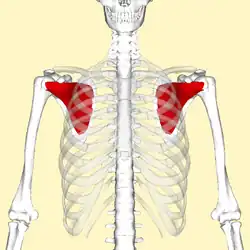

![]() Subscapularis muscle (in red). Ribs are shown as semi-transparent. Anterior view. | |

The subscapularis is a large triangular muscle which fills the subscapular fossa and inserts into the lesser tubercle of the humerus and the front of the capsule of the shoulder-joint.